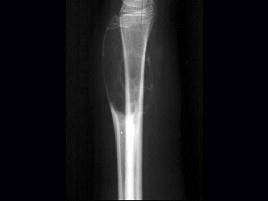

问题 男,17岁,来右前臂疼痛,肿胀近2年,2周前疼痛加剧,查体右前臂压痛明显,皮肤稍显红肿,结合图像,最可能诊断是?(?)

选项 A.骨囊肿 B.骨巨细胞瘤 C.动脉瘤样骨囊肿 D.软骨瘤 E.骨血管球瘤

答案 C